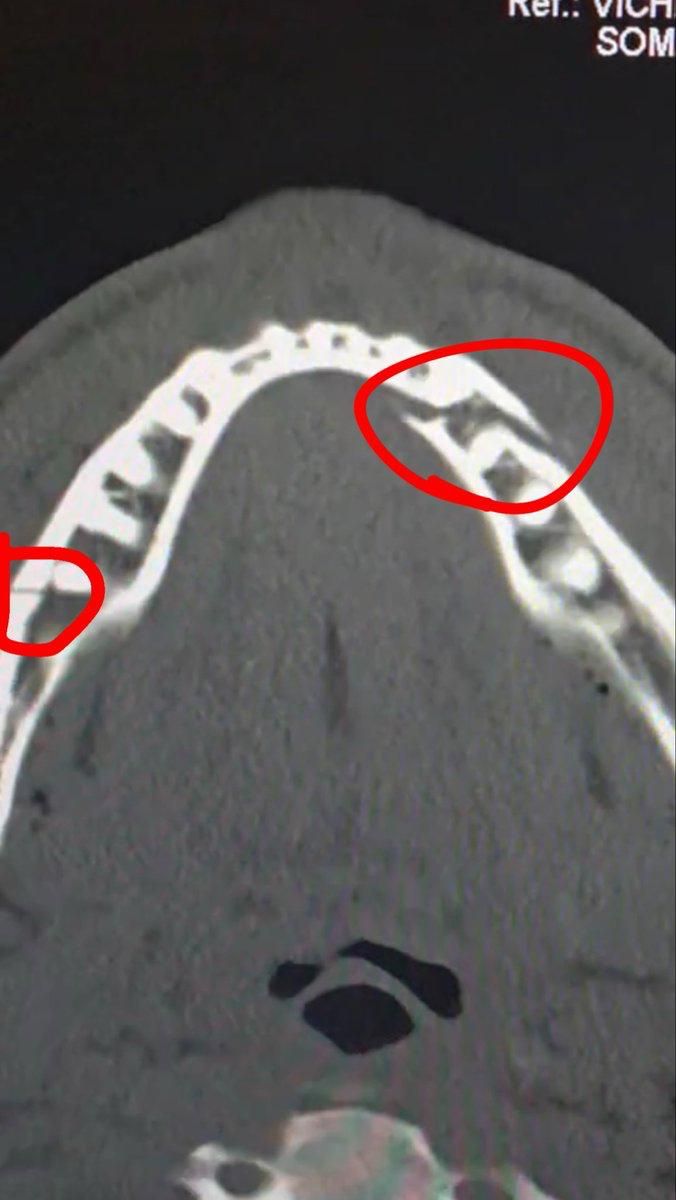

Жейк Полнинг ўтказиб юборилган зарба оқибатида жағи синиб кетгани айтилмоқда + ФОТО

Блогер-боксчи супероғир вазнда собиқ жаҳон чемпиони Энтони Жошуага қарши нокаутли жангидан кейин шифохонага олиб кетилган.